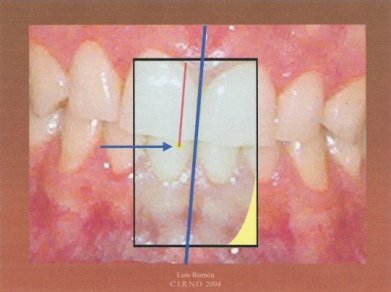

3.- Trazamos una línea con el rotulador sobre el papel celo de tal manera que comienza en el punto que marcamos en el primer paso, visto por transparencia, y asciende paralelo a la línea media facial del paciente. Este paso debe realizarse con mucho cuidado pues de él depende el éxito del procedimiento.

4.- Invitamos al paciente a realizar una lateralidad derecha. Es aconsejable que sea lo más amplia posible siempre y cuando el trayecto sea rectilíneo. Marcamos sobre el papel celo un punto encima del que pintamos en el primer paso.